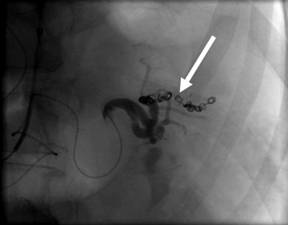

The relevant splenic artery branch was selectively embolized using coils, which halted the bleeding (Figure 4).

Figure 4. Angiography image demonstrating successful occlusion of the splenic artery branch with metal coils (arrowed). |

Successful embolization led to stabilisation of the patient’s haemodynamic status and consequently splenectomy was avoided.